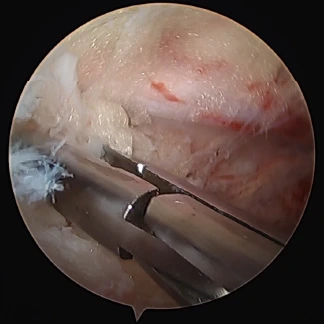

当院では、膝関節、肩関節(腱板修復術、バンカート修復術)、手指(手根管開放術)、股関節の疾患に対して「関節鏡視下手術」を行っています。関節鏡視下手術とは、まず手術をする関節の周囲に6~7mmの皮膚切開を数個作り、この小さな切開口から細いカメラ(内視鏡)や手術器具を関節内に入れて、モニターで内部を目視しながら行う手術のことです。関節鏡を用いる手術では、手術時の切開口が小さくて済むので、術後の回復が早いのが特徴です。体力的にも美容的観点からも患者さんの負担が小さいなどのメリットもあります。

前十字靱帯の損傷はスポーツ時の外傷(ケガ)によるものが多く、そのまま放置していると、半月板や軟骨などの正常な組織が傷つく場合があります。当院では、関節鏡視下手術としては比較的難度の高い「膝前十字靱帯再建術」(ACL)、「膝後十字靱帯再建術」(PCL)の豊富な症例実績を有しています。

腰椎椎間板ヘルニアの術中画像